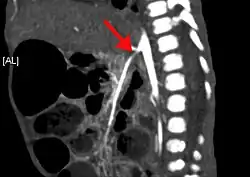

| CT angiogram demonstrating stenosis of the superior mesenteric artery. | |

Abdominal angina is diagnosed by identifying stenosis with imaging.[10] Since the symptoms of abdominal angina overlap with various other disorders, other causes of symptoms are ruled out as a part of the diagnostic process. Gastric ulcers, abdominal aortic aneurysms, and gastrointestinal cancers can have similar symptoms and can be ruled out by esophagogastroduodenoscopy, CT scans, or MR angiogram. Other differential diagnoses include GERD, dietary or food sensitivities, constipation, pancreatitis, abdominal abscess, appendicitis, irritable bowel syndrome, gastroenteritis, hepatitis, and inflammation of the gastrointestinal system.[11] Duplex ultrasound, MR angiography, angiography, and computed tomography angiography can be used to help confirm the diagnosis of abdominal angina.[3] Duplex ultrasound may be used to screen for abdominal angina but is not ideal for visualizing stenosis. Angiography, MR angiography, or CT angiography can be used to further visualize the celiac and mesenteric arteries.[12]